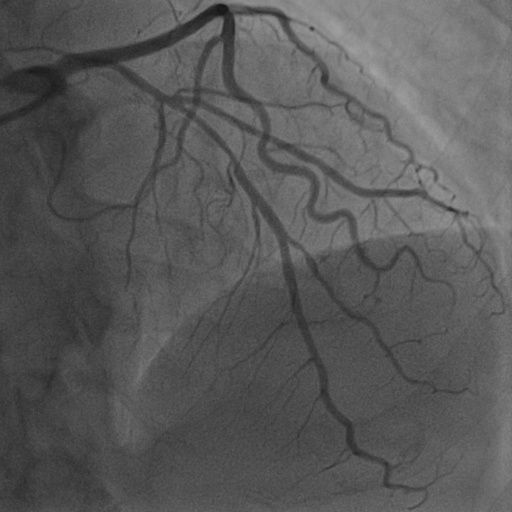

Hessian prior loss .

To test the effect of the Hessian prior loss, we remove the Hessian prior loss. As a result, the segmentation performance, as shown in Table 2, also decreases the Dice score by 0.1006. The comparison between the without and with is shown in Figure 9 (b), where the orange area indicates the difference between them. The zoom-in patch shows that our model predicts less noticeable vascular regions incorporating the Hessian prior loss .